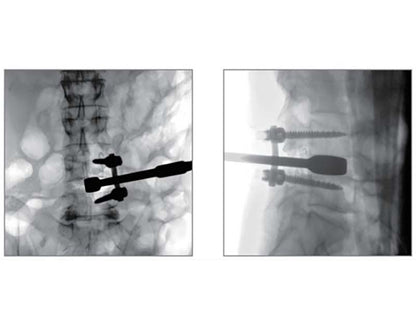

Higher signal coversion efficiency of FPD ensures higher image quality and lower dose.

16 bits depth determines maximum 65536 greyscale value, providing HD resolution for revealing more anatomical details.